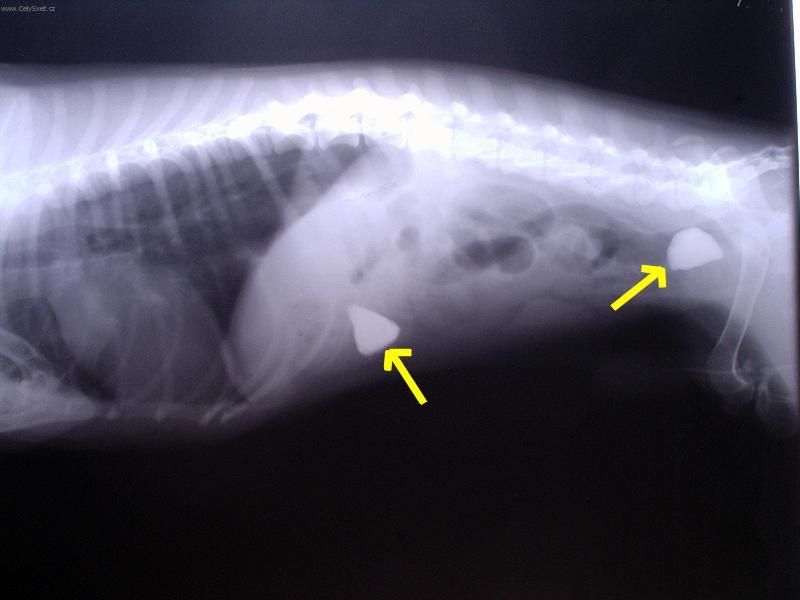

Foto galerie (fotky, obrazky): Cizí tělesa v zažívacím traktu a kostní trus.

Clanek: Cizí tělesa v zažívacím traktu a kostní trus.